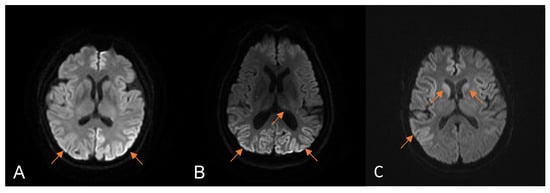

| Restricted diffusion in the first MRI, n (%) | 13 (72.2%) |

| MRI fulfilled the WHO criteria for CJD, n (%) | 10 (55.6%) |

| Restricted diffusion on occipital lobe, n (%) | 10 (55.6%) |

| Restricted diffusion in the serial MRI, n (%) | 17 (94.4%) |

| MRI fulfilled the WHO criteria for CJD, n (%) | 16 (88.9%) |

| Restricted diffusion on occipital lobe, n (%) | 14 (77.8%) |

| Typical hyperintensity on DWI, n (%) | 8 (88.9%) | 14 (93.3%) | 1.000 |

| DWI hyperintensity on occipital lobe, n (%) | 6 (66.7%) | 11 (73.3%) | 1.000 |

| DWI hyperintensity on basal ganglia, n (%) | 5 (55.6%) | 6 (40%) | 0.675 |